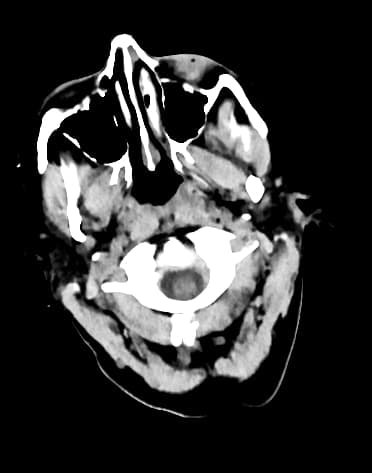

Axial non-contrast

Nhồi máu vùng phân bố động mạch não giữa bên phải với dấu hiệu động mạch não giữa tăng tỷ trọng

- Giảm tỷ trọng nhẹ ở vỏ não đảo (insular cortex) bên phải và thùy thái dương liền kề, kèm theo mất phân biệt ranh giới vỏ-tủy (dấu hiệu dải vỏ đảo – insular ribbon sign), xóa nhẹ các rãnh não, cùng với dấu hiệu động mạch não giữa (MCA) tăng tỷ trọng bên phải, phù hợp với nhồi máu thiếu máu cục bộ cấp sớm trong vùng phân bố động mạch não giữa (MCA territory) bên phải.

- Không thấy hình ảnh xuất huyết nội sọ cấp tính.

Nhồi máu thiếu máu cục bộ cấp sớm trong vùng phân bố động mạch não giữa (MCA) bên phải có thể biểu hiện rất kín đáo trên chụp CT không tiêm thuốc cản quang. Trường hợp này cho thấy giảm tỷ trọng nhẹ ở vỏ não đảo bên phải và thùy thái dương liền kề, mất phân biệt ranh giới vỏ-tủy (dấu hiệu dải vỏ đảo – insular ribbon sign), xóa nhẹ các rãnh não và dấu hiệu động mạch não giữa tăng tỷ trọng – tất cả đều gợi ý tắc mạch lớn sớm. Điểm ASPECTS ước tính là 9, phản ánh những thay đổi thiếu máu sớm còn hạn chế. Việc nhận biết các dấu hiệu CT sớm này là rất quan trọng để can thiệp kịp thời bằng tiêu sợi huyết hoặc can thiệp nội mạch.

Nhồi máu vùng phân bố động mạch não giữa bên phải với dấu hiệu động mạch não giữa tăng tỷ trọng (right MCA territory infarct with dense MCA sign)